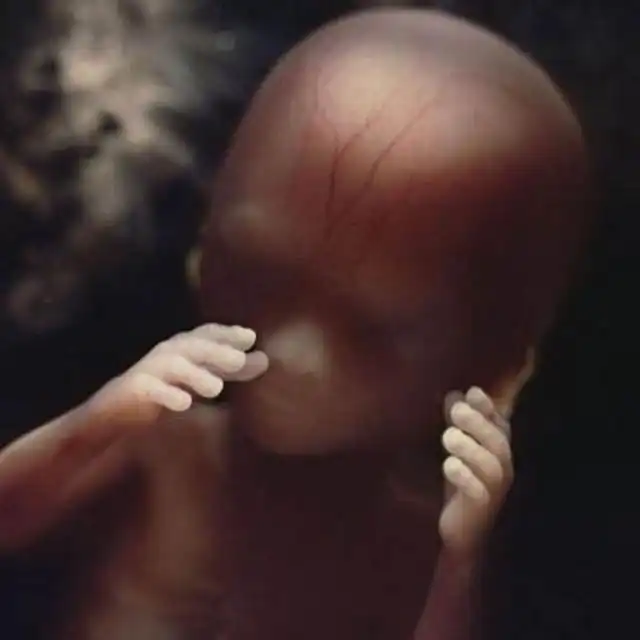

18 недель. Около 14 см. Зародыш теперь может воспринимать звуки из внешнего мира.

19 недель..

20 недель. Около 20 см. На голове уже начинают появляться волосы.